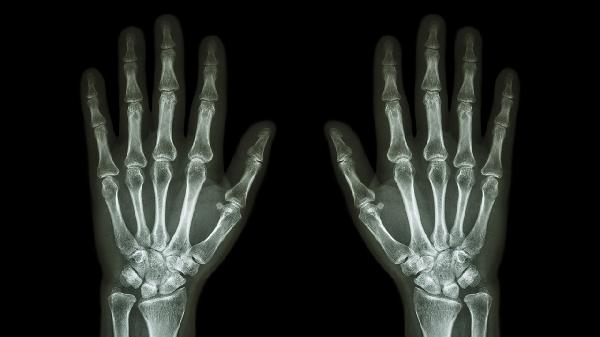

大拇指关节突出可能与遗传因素、外伤、骨关节炎、类风湿关节炎、腱鞘囊肿等原因有关。通常表现为关节肿胀、疼痛、活动受限等症状,可通过影像学检查明确诊断。